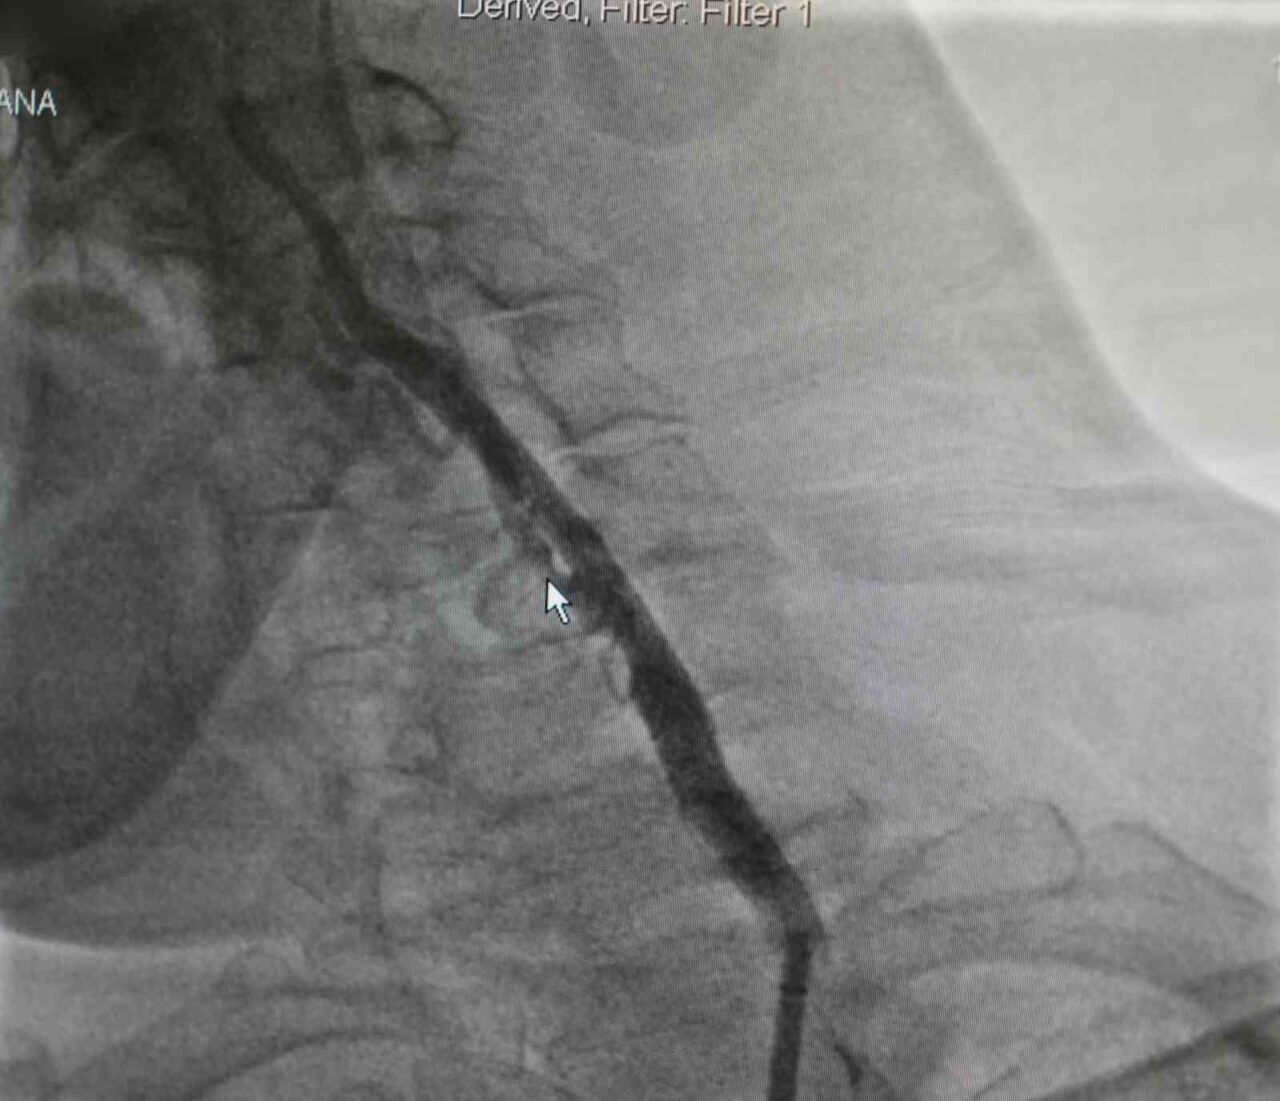

Samsun’da yaşayan Zekai Bozyel (71), 15 yıl önce bypass ve kalp kapak ameliyatı geçirdi. Rutin kontrolleri devam eden Bozyel, 20 gün önce kolunda güçsüzlük şikayetiyle nöroloji servisine yatırıldı. Yapılan tetkiklerde hastanın sağ boyun damarında yüzde 30, sol boyun damarında ise yüzde 90 oranında darlık tespit edildi. Sol taraftaki ciddi darlığın hastanın felç geçirmesine neden olduğu belirlendi. Hastanın daha önce kronik akciğer rahatsızlığı bulunması ve geçirdiği ameliyatlar nedeniyle anestezi açısından yüksek risk taşıdığı değerlendirildi. Bunun üzerine hastanın durumu kardiyoloji ekibi tarafından yeniden ele alındı. Akabinde Medicana International Samsun Hastanesi Kardiyoloji Uzmanı Dr. Öğr. Üyesi Ahmet Yanık, boyun damarında yüzde 90 darlık tespit edilen ve daha önce baypas ile kalp kapak ameliyatı geçiren hastaya ameliyatla kasıktan girerek uygulanan anjiyografik yöntemle stent yerleştirdi. Gerçekleştirilen başarılı müdahaleyle yeniden felç riskinin önüne geçildiğini belirtti.

Hastanın filmlerini inceleyip muayenesini yaptıklarını belirten Dr. Öğr. Üyesi Ahmet Yanık, “Zekai bey 15 yıl önce bypass ve kalp kapak ameliyatı olmuş, rutin takiplerinde devam eden bir hastamız. 20 gün önce nöroloji servisine yatıyor. İnme hikayesi ve kolunda güçsüzlük var. Yapılan tetkiklerinde boyun damarında darlık saptanıyor. Sağdaki boyun damarında yüzde 30, soldaki boyun damarında ise yüzde 90 civarında bir darlık var. Bu felç geçirmesine sebep olan bir darlık. Öncelikle ameliyat düşünüldü ancak kronik akciğer öyküsü ve diğer rahatsızlıkları nedeniyle anestezi açısından riskli bulundu. Biz damarın bu şekilde bırakılmasının daha riskli olacağını düşündük. Hastamızla görüşerek işlemi yapmaya karar verdik. Başarılı bir şekilde soldaki boyun damarına kasıktan girerek, herhangi bir kesi yapmadan anjiyografik olarak stent yerleştirdik. İşlem sonrası herhangi bir sorun yaşamadık ve hastamızı taburcu ettik. Müdahale edilmemesi durumunda daha ciddi bir felç riski söz konusuydu” dedi.